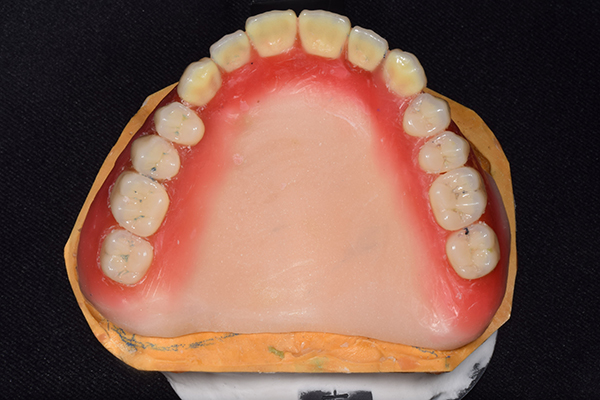

入れ歯は極力薄くするために金属を使用しました。しっかり噛める様にするため、ノンメタルクラスプデンチャーにはしませんでした。

上の入れ歯(表)

上の入れ歯(裏)